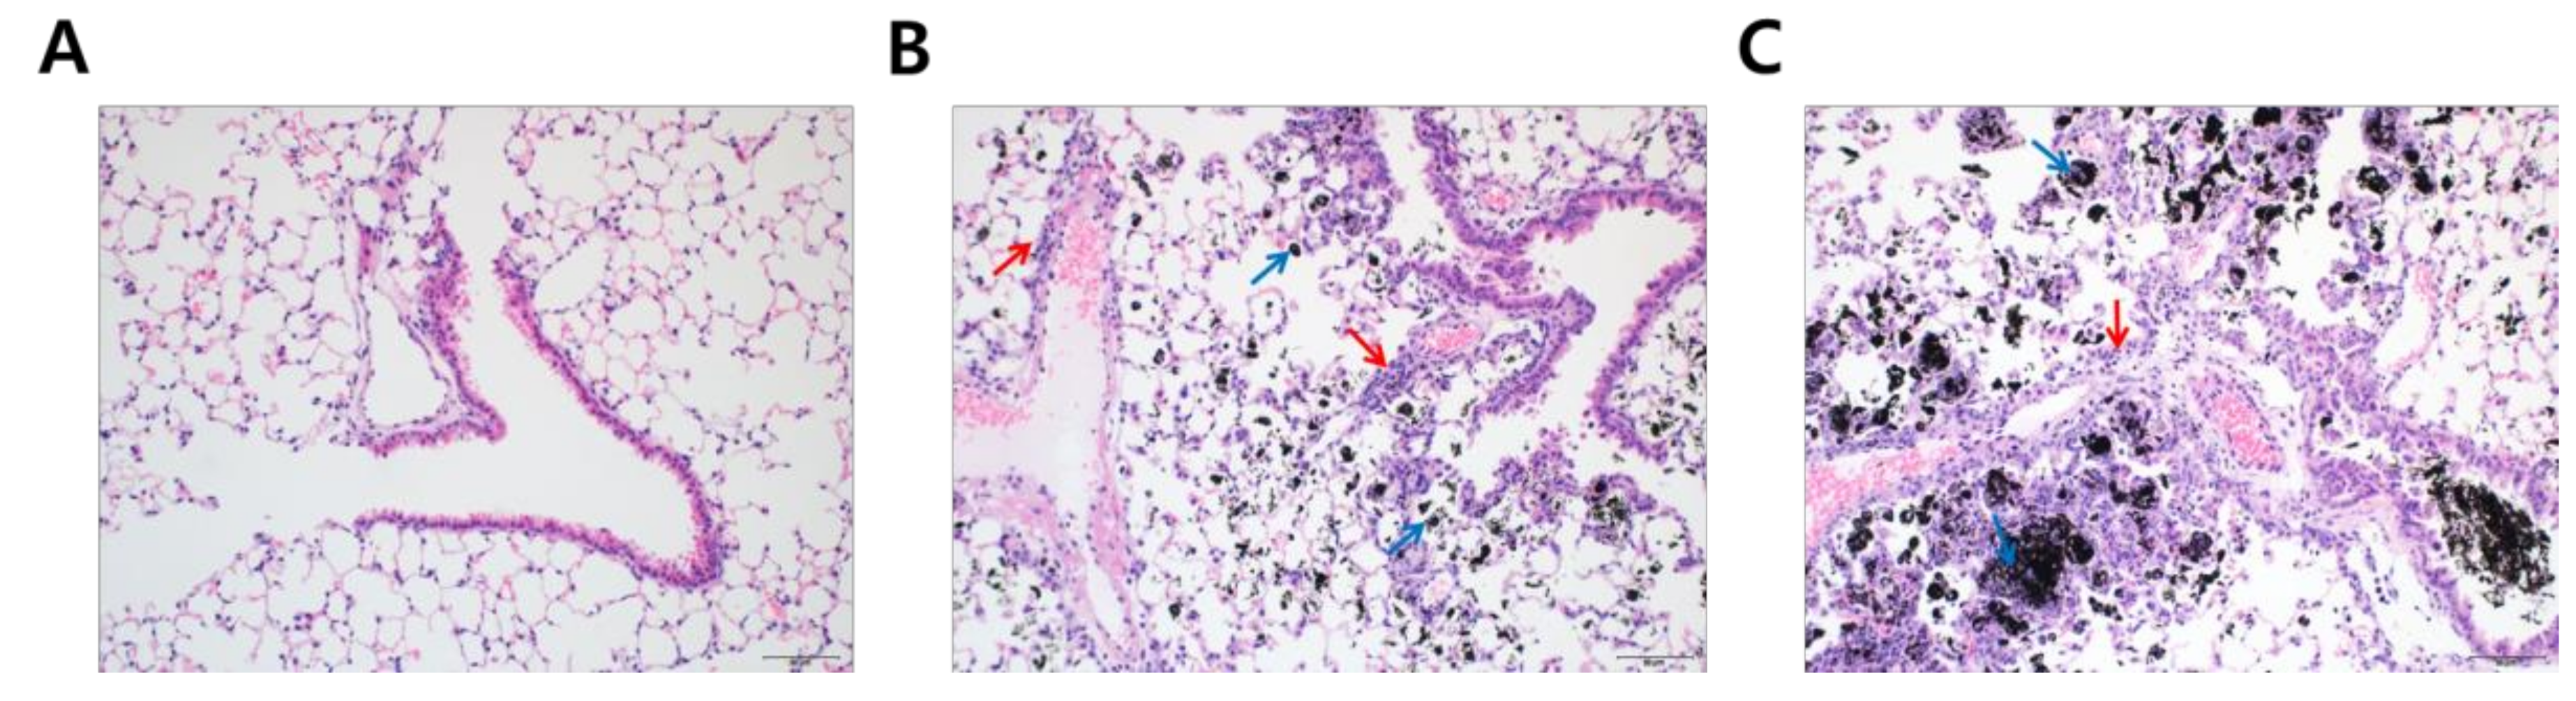

3.2. Histological Analysis